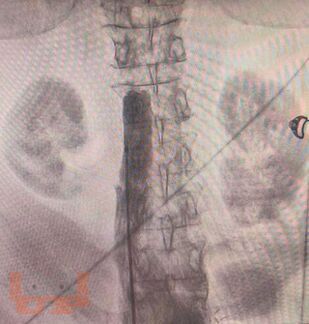

Современные методы диагностики заболеваний бассейна нижней полой вены

Учебное пособие содержит основные сведения о анатомии и физиологии венозной системы нижних конечностей, морфологии и патофизиологии данных заболеваний, современных методах диагностики. Рассчитано на ординаторов и слушателей ФДПО хирургических специальностей.